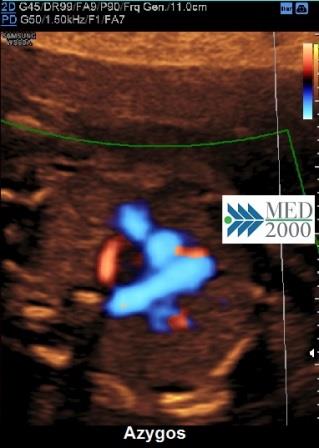

In questa posizione è possibile confondere l'arteria succlavia aberrante con l'azygos. In tal caso la diagnosi differenziale tra i due vasi è possibile per due segni:

- l'origine dell'azygos non è all'apice della "V"

- l'azygos è connessa alla vena cava superiore